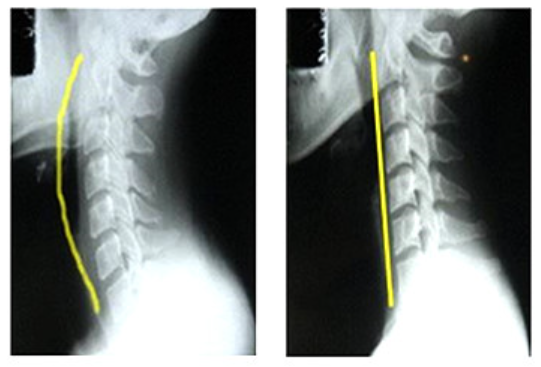

원래 아래와 왼쪽그림같이 c 커브르 그려야 하는데

저는 오른쪽의 그림처럼, 일자의 목뼈 모습이 보이고 있었습니다.